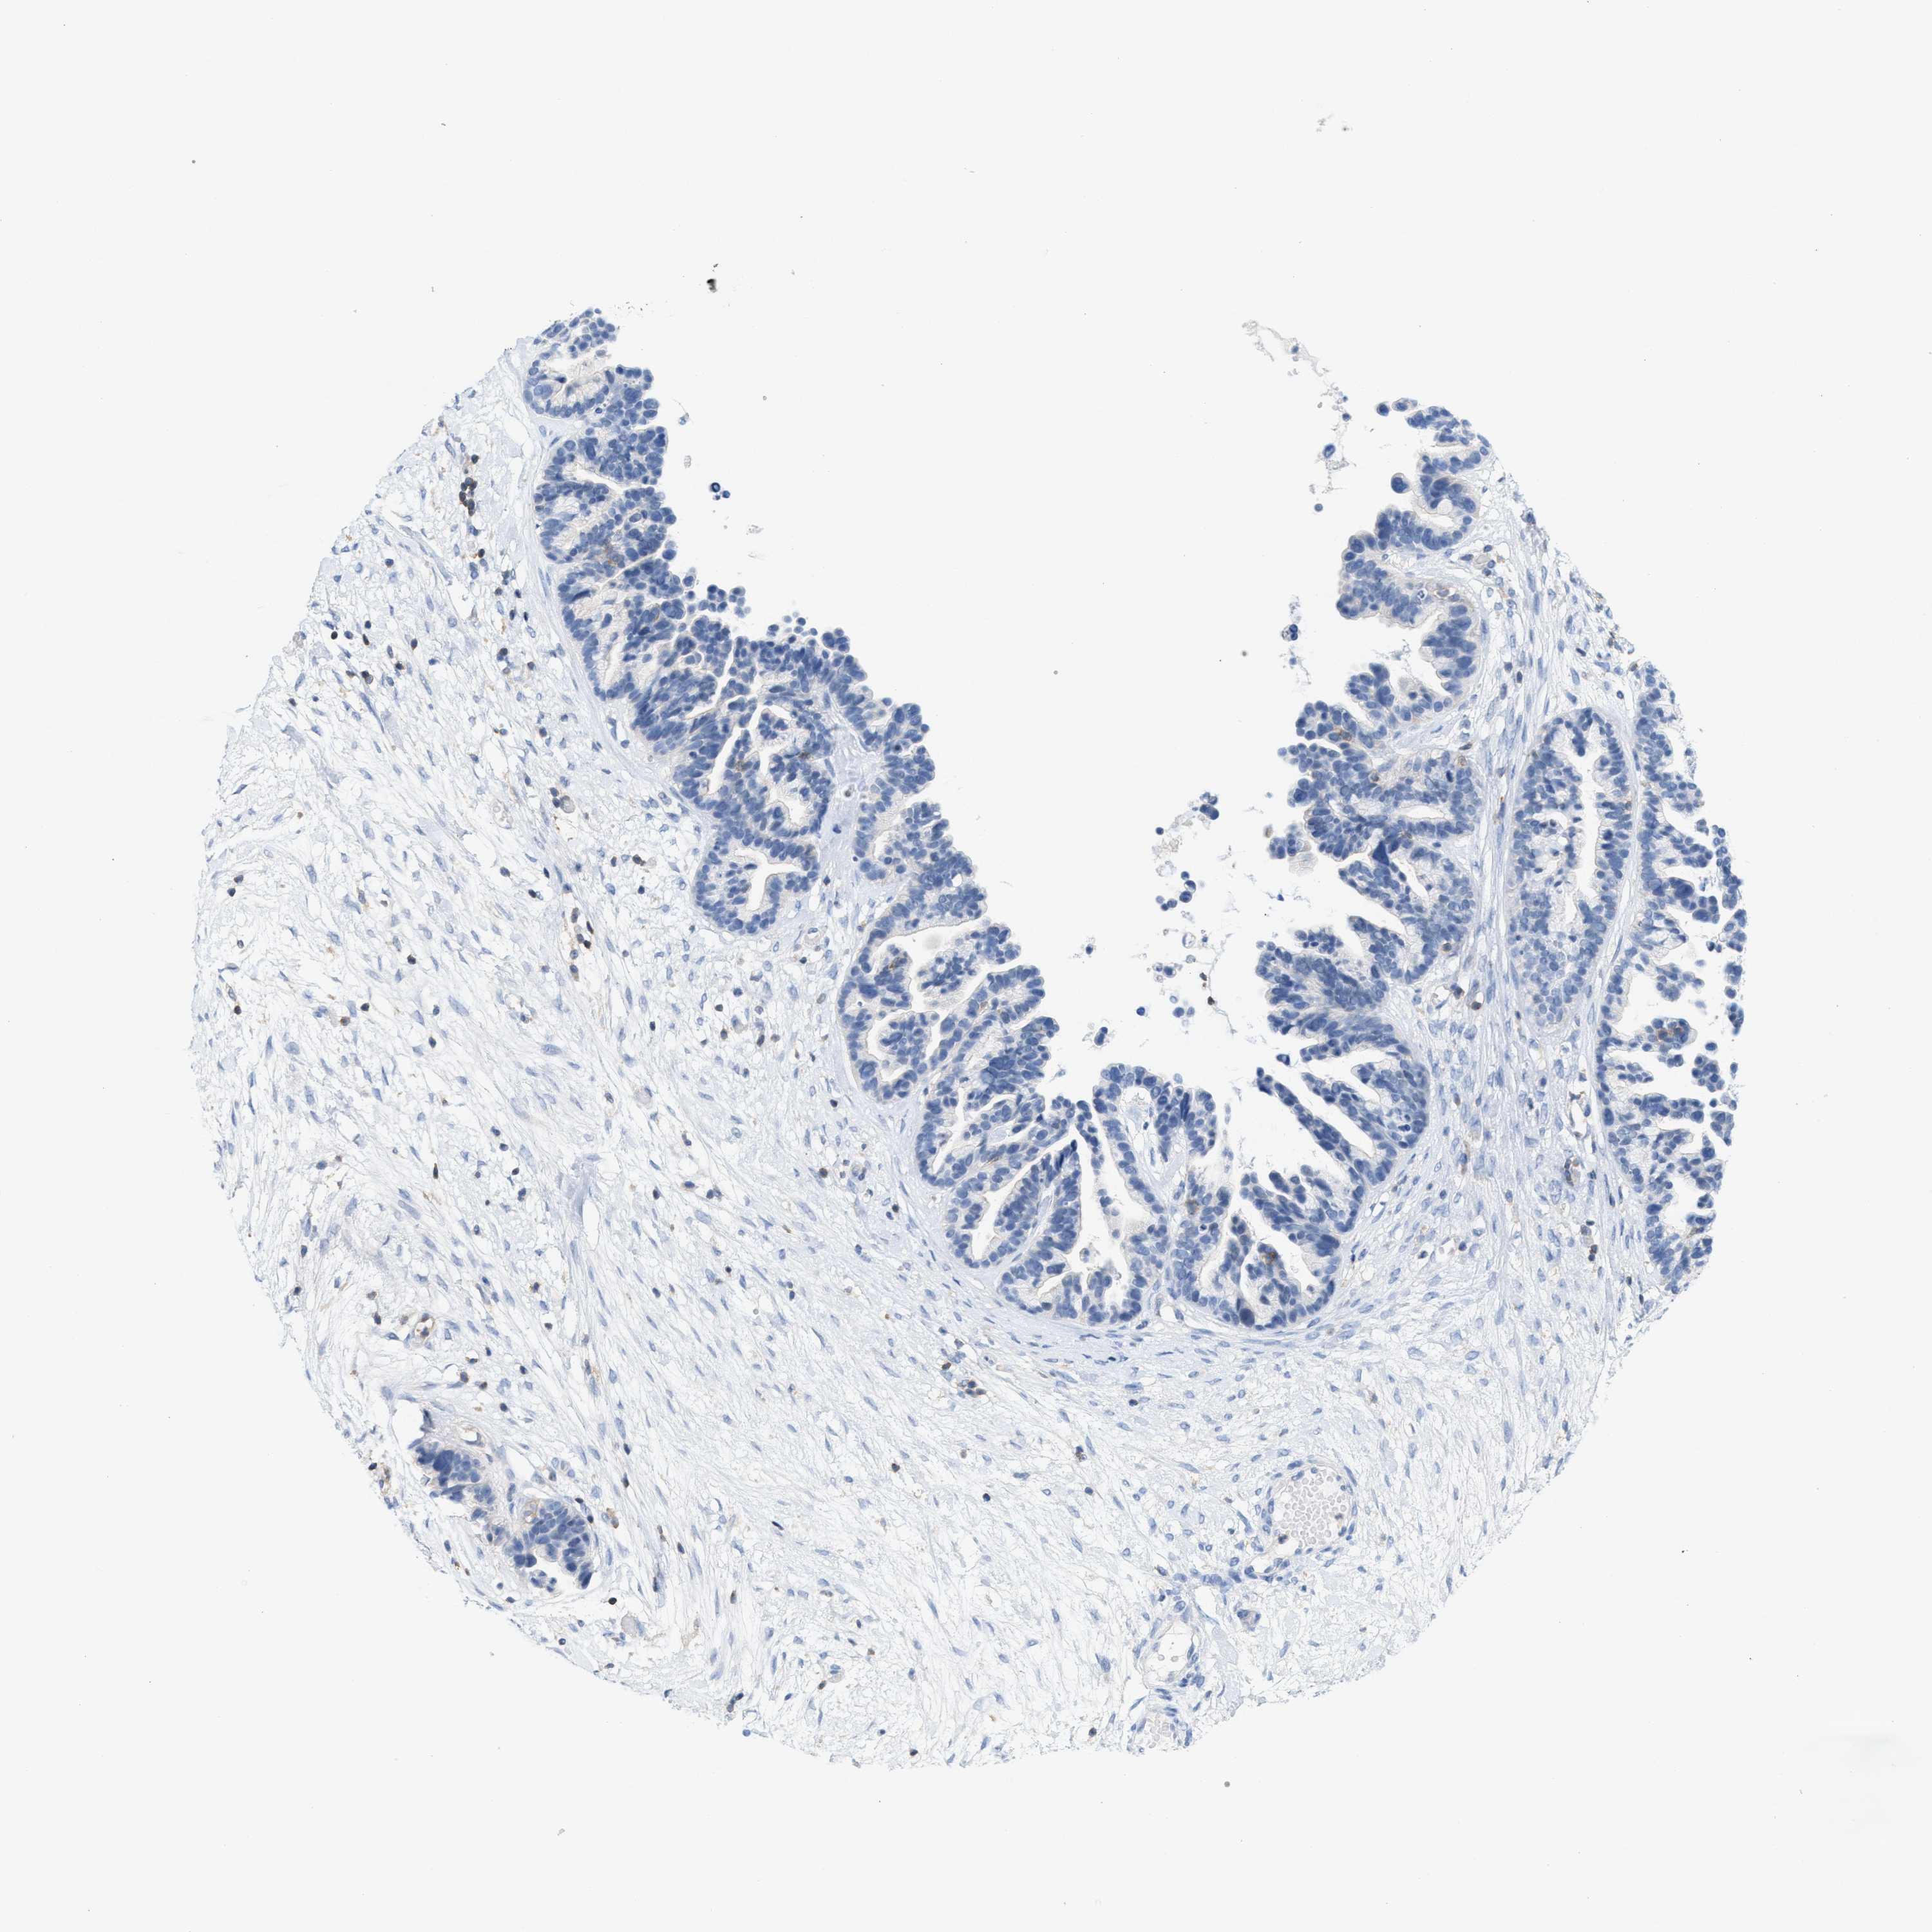

OVARIAN CANCER - Protein expressioni

A mouse-over function shows sample information and annotation data. Click on an image to view it in a full screen mode. Samples can be filtered based on level of antibody staining by selecting one or several of the following categories: high, medium, low and not detected. The assay and annotation is described here.

Note that samples used for immunohistochemistry by the Human Protein Atlas do not correspond to samples in the TCGA dataset.

Antibody stainingi

Antibody staining in the annotated cell types in the current human tissue is reported as not detected, low, medium, or high, based on conventional immunohistochemistry profiling in selected tissues. This score is based on the combination of the staining intensity and fraction of stained cells.

Each image is clickable and will lead to virtual microscopy that enables deeper exploration of all samples and also displays staining intensity scores, fraction scores and subcellular localization as well as patient and tissue information for each sample.

Antibody HPA018467

Antibody CAB005247

Cystadenocarcinoma, serous, NOS

Carcinoma, endometroid

Cystadenocarcinoma, mucinous, NOS

Carcinoma, NOS